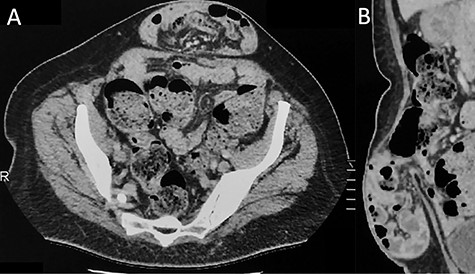

A 59-year old woman was referred with an infra-umbilical lump that had been progressively increasing in size and causing discomfort. A partly reducible midline ventral hernia was clinically diagnosed, containing loops of small bowel on CT-scan (Fig. 1). No other associated hernia defect was demonstrated. Laparoscopic repair was planned using a standard lateral trans-abdominal approach, with placement of the three ports at the level of the left anterior axillary line [4]. Incidentally, two associated ALHs were identified on each side of the main ventral hernia defect (Fig. 2). The peritoneum was incised transversally above the arcuate lines allowing both peritoneal folds to be completely reduced (Fig. 3). Peritoneum dissection was extended caudally with opening of the pre-peritoneal space, similar to a TAPP technique, for ideal mesh placement.

Contrast-enhanced CT imaging demonstrating an incarcerated ventral hernia containing small bowel loops. There is no evidence of associated arcuate line hernia (ALH) between the posterior rectus sheath and the rectus muscle. (A) Axial plane and (B) sagittal plane.